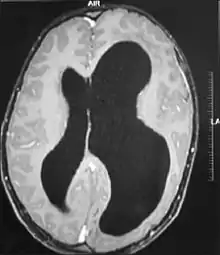

| MRI images showing megalencephaly in four family members who all have unusually large skulls (the family is affected by an autosomal recessive syndrome caused by a KIF7 mutation that induces multiple epiphyseal dysplasia)[1] | |

A mutation in the PI3K-AKT pathway is believed to be the primary cause of brain proliferation and ultimately the root cause of megalencephaly. This mutation has produced a classification of brain overdevelopment that consists of two syndromes including megalencephaly-capillary malformation (MCAP) and megalencephaly-polydactyly-polymicrogyria-hydrocephalus (MPPH).[4] Megalencephaly is usually diagnosed at birth and is confirmed with an MRI.

A neurological exam will then be performed using the technology of an MRI machine in order to confirm the diagnosis of megalencephaly. These imaging tests give detailed information regarding brain size, volume asymmetry and other irregular developments linked with MCAP, MPPH and hemimegalencephaly.[2][21]